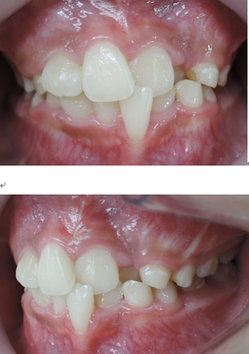

今回の症例は、悪い歯並びの代表例である八重歯です。

歯並びが悪いだけでなく、困ったことに犬歯から奥歯にかけて歯が嚙み合っていない開咬の状態です。

一般的な矯正の治療法では中心から4番目の歯を抜いて隙間をつくり、飛び出した犬歯を並べて治療します。

しかし、この矯正方法は歯を横に動かす治療法なので、噛んだときにできる奥歯の上下の隙間を治すのが苦手です。

当院ではマルチループ(MEAW法)という上の写真で装着しているようなクネクネ曲がったワイヤーを使用して、上下の隙間を埋めていくことで歯並びを整えます。